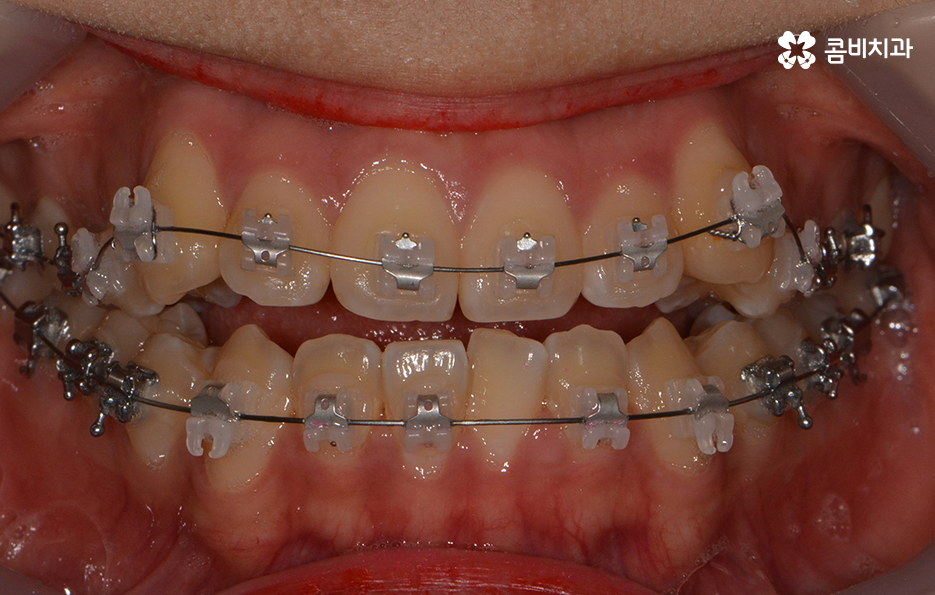

클리피씨 교정을 통해서 덧니가 개선되고 있는 경과

앞서 치아교정에 걸리는 기간은 어떤 교정 장치를 선택하냐에

따라서 차이가 발생된다고 말씀을 드렸는데요.

요즘 선호도가 높은 교정 장치로는 클리피씨 교정이 대표적입니다.

클리피씨 교정의 경우에는 일반적인 교정 방법에 비해서

진료 기간을 단축시킬 수 있다는 장점이 있는데

자가 결찰 장치로 서서히 치아를 지속적으로 이동시켜서

초기 통증은 줄이고 교정 기간의 단축이 가능합니다.

또한 교정 장치의 재질이 세라믹이기 때문에

심미적이라는 장점이 있으며 철사로 인한 찔림이

없다는 점에서도 편리함이 있는 장치입니다.